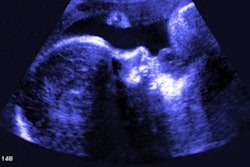

China-based ultrasound firm SonoScape has launched a new generation of ultrasound scanners called Elite that have built-in artificial intelligence (AI) capabilities.

The Elite series utilizes SonoScape's Wis+ intelligent ultrasound platform. Its AI-driven features, including S-Fetus, Auto OB, and lucid imaging technologies, all come standard for the series.

The new line of scanners has four times the data processing capability and 10 times the system response rate of older models, the company noted. The scanners can also perform advanced rendering modes, including S-Live Silhouette and Color 3D.